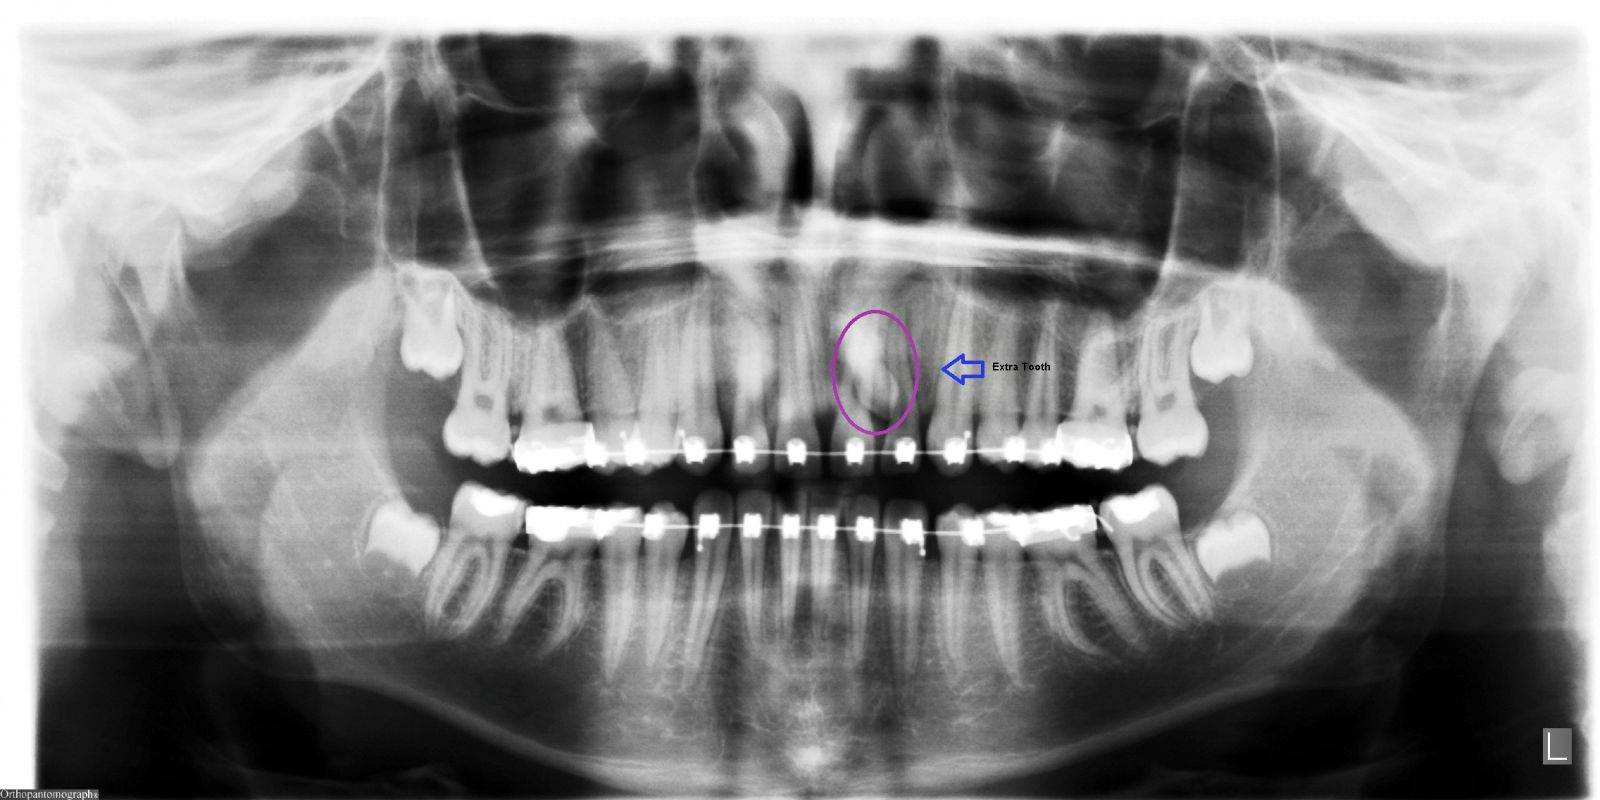

Extra Teeth

- It is fairly rare that there are extra teeth (also known as supernumerary teeth).

- One of the most common areas that this occurs is at the second from the centre teeth on the upper teeth (upper lateral incisors).

- When there are extra teeth, it is simply due to genetics and it will cause severe crowding if such an extra tooth is allowed to stay in the mouth.

- Normally an extra tooth will be removed as soon as is practical.

- Another common area for extra teeth is at the wisdom teeth (third molars).